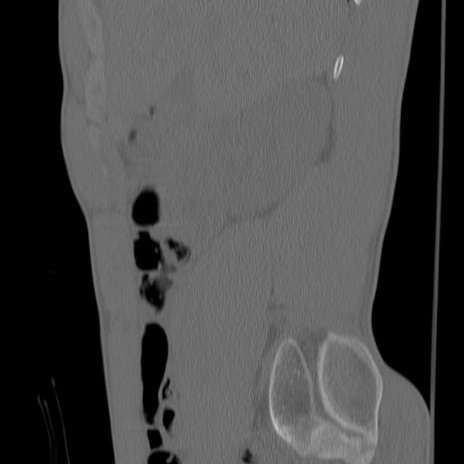

症例3 腰椎CT(矢状断像)

腰椎CT

冠状断像